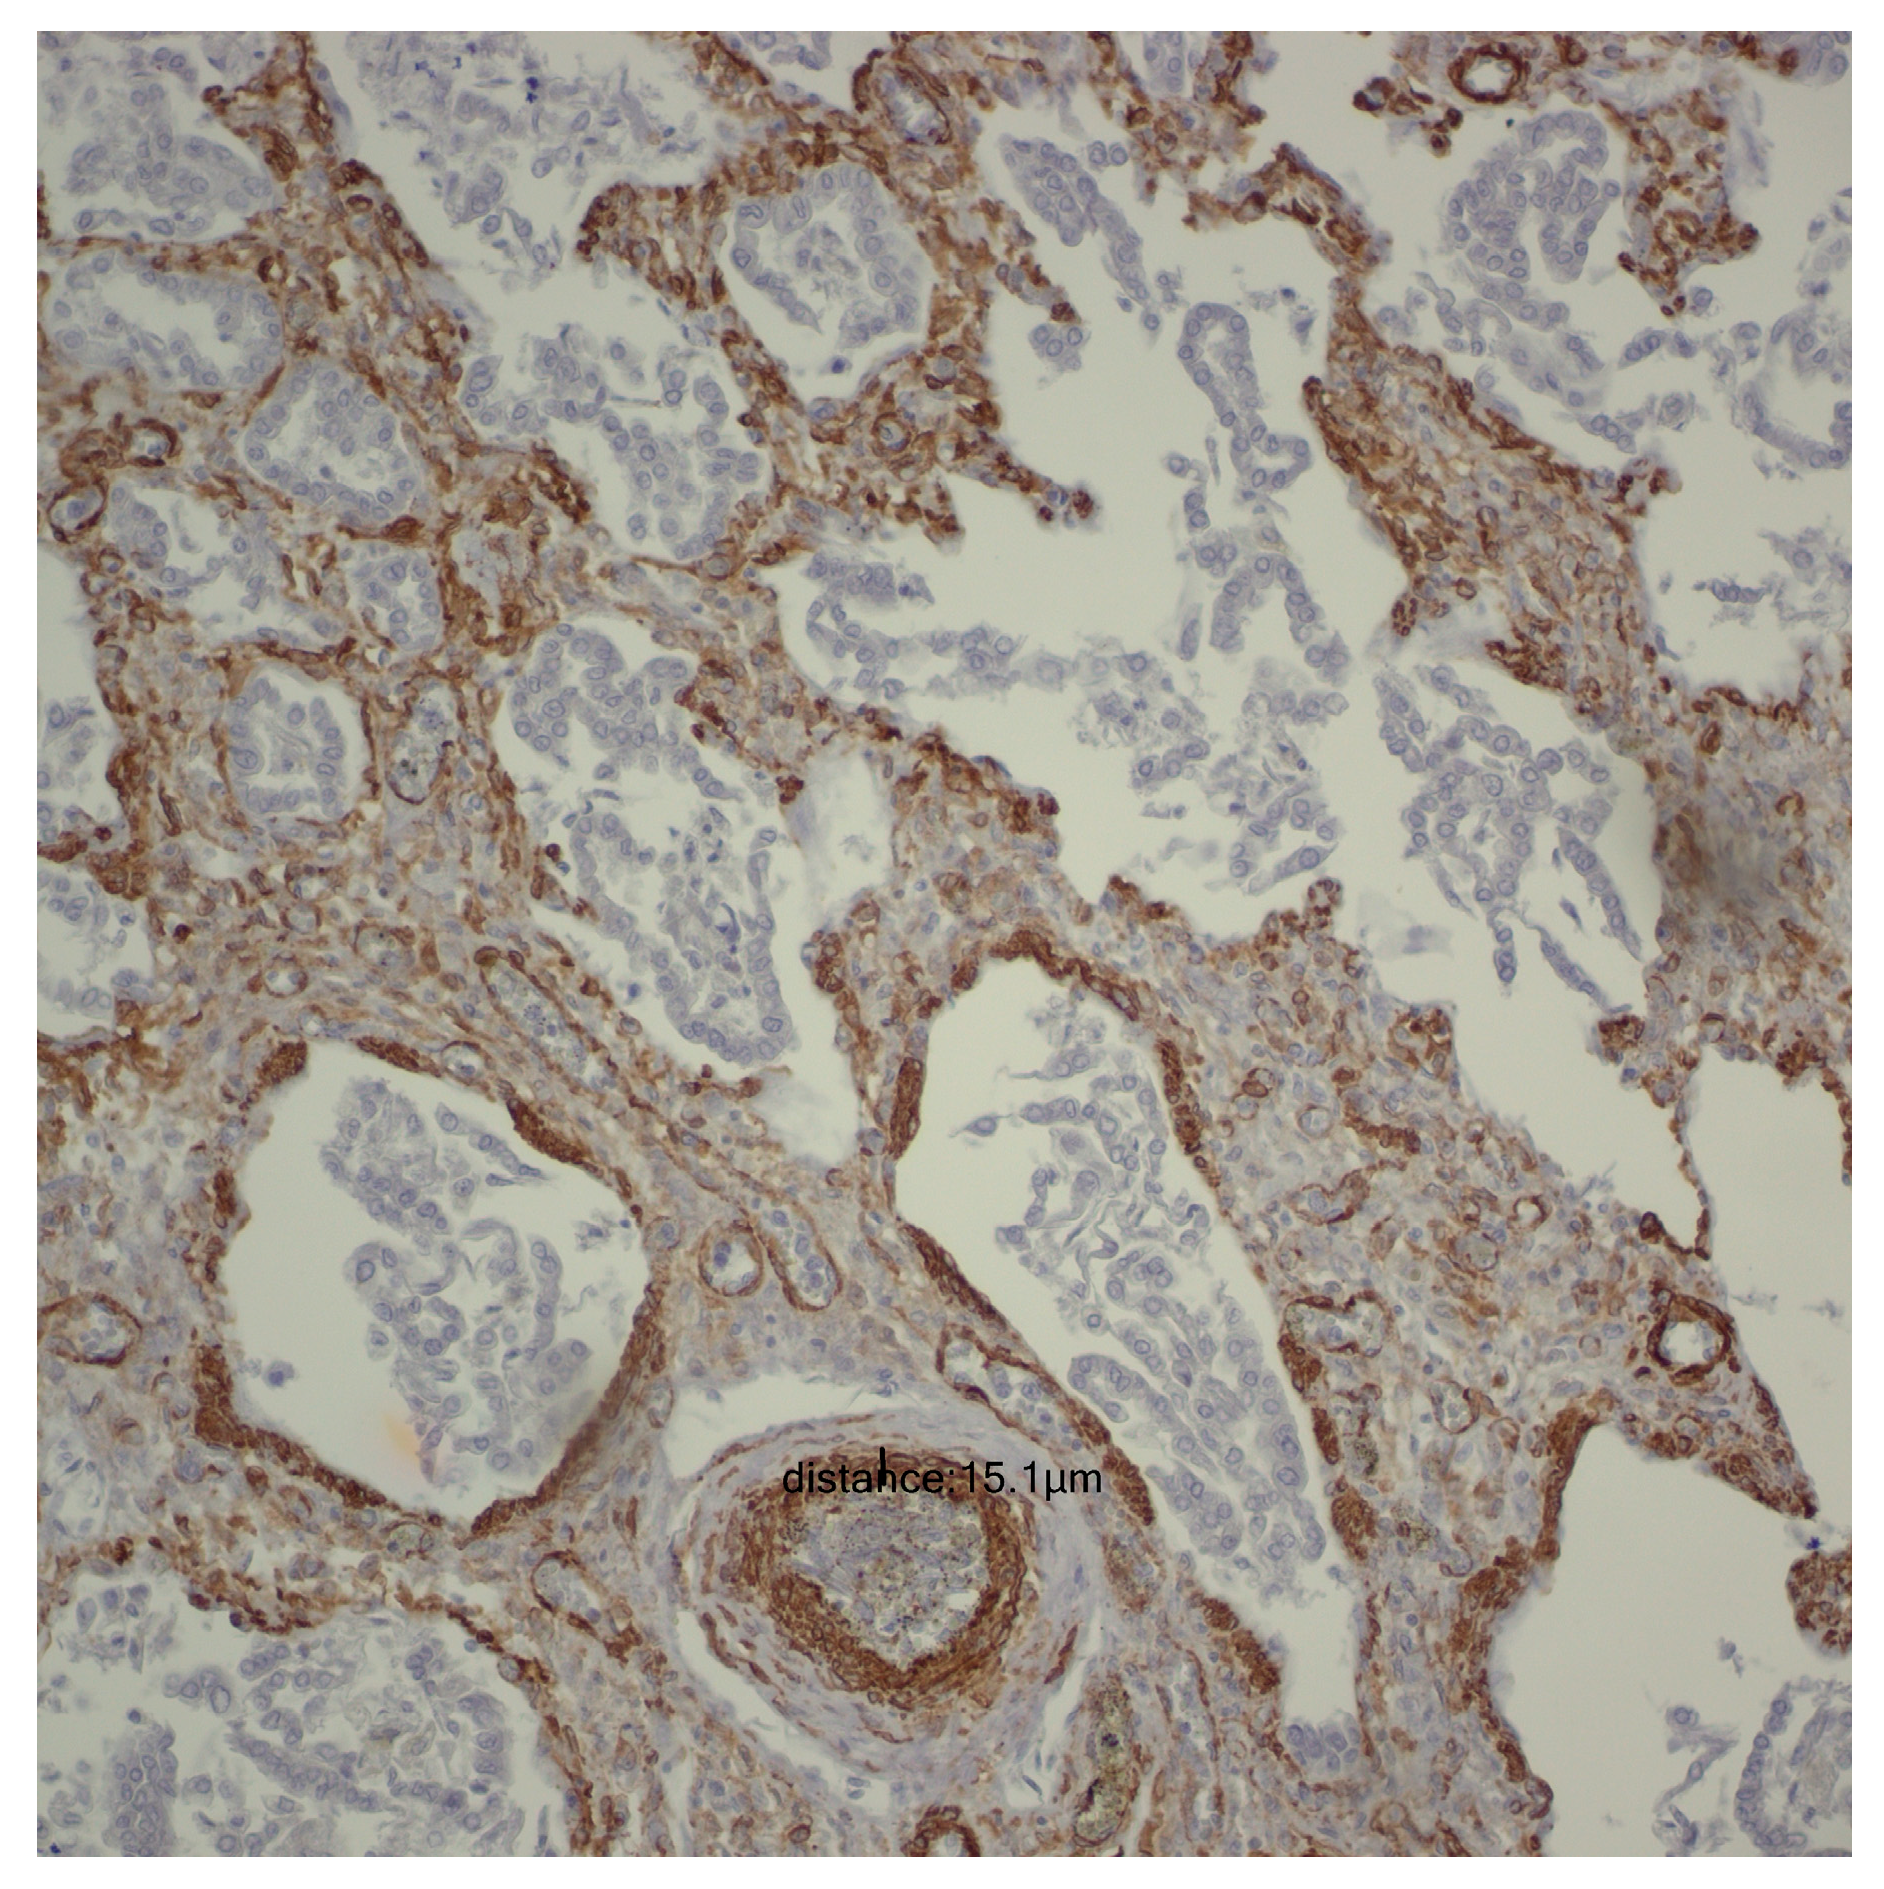

For the evaluation of the media layer of the vascular walls, a vertical line was drawn between the highest point and the lowest point, recording the values obtained for each individual case. To prevent inaccuracies in measuring the arteriolar media, tangentially captured vascular structures were deliberately avoided, with measurements taken exclusively at the level of transversely captured vascular structures (Figure 1).

Figure 1.

Smooth Muscle Actin (SMA) immunoreactivity at 200× magnification, illustrating the thickness of the vascular media.

After evaluating pulmonary microvascularization, we proceeded to examine larger vascular structures of the arteriolar type and assess the thickness of the arteriolar media by analyzing the SMA immunohistochemical marker (please refer to the evaluation protocol). We aimed to investigate whether the thickness of the arteriolar media was affected by the number of days of life and oxygen treatment, and we noted a positive correlation between them. As life expectancy rises, there is a tendency for an increase in the thickness of the arteriolar media (r = 0.22; p = 0.008) (Figure 8).

A positive correlation is evident between the duration of oxygen therapy and the thickening of the arteriolar media, signifying a rise in thickness with prolonged oxygen therapy (r = 0.20; p =0.017) (Figure 9).